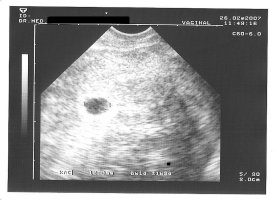

war ja gestern wieder beim FA.

Es ist alles soweit ok mit dem Zwerg. Da ich hin und wieder ein starkes ziehen im Bauch hab hat sie gleich mal geschaut, ob es dem kleinen Wurm gut geht, also ein US außer der Reihe. Gemessen hat sie daher nicht, aber ein Bild ahb ich bekommen.

Hab jetzt 1,5 Kilo zugenommen, Blutdruck ist ok, also alles beim Besten. Am 10.04. geh ich zur Feindiagnostik und der nächste Termin beim FA ist am 04.04.

Hier noch ein Bildchen:

• 14,6SSW.jpg

14,6SSW.jpg

182,5 KB · Aufrufe: 995